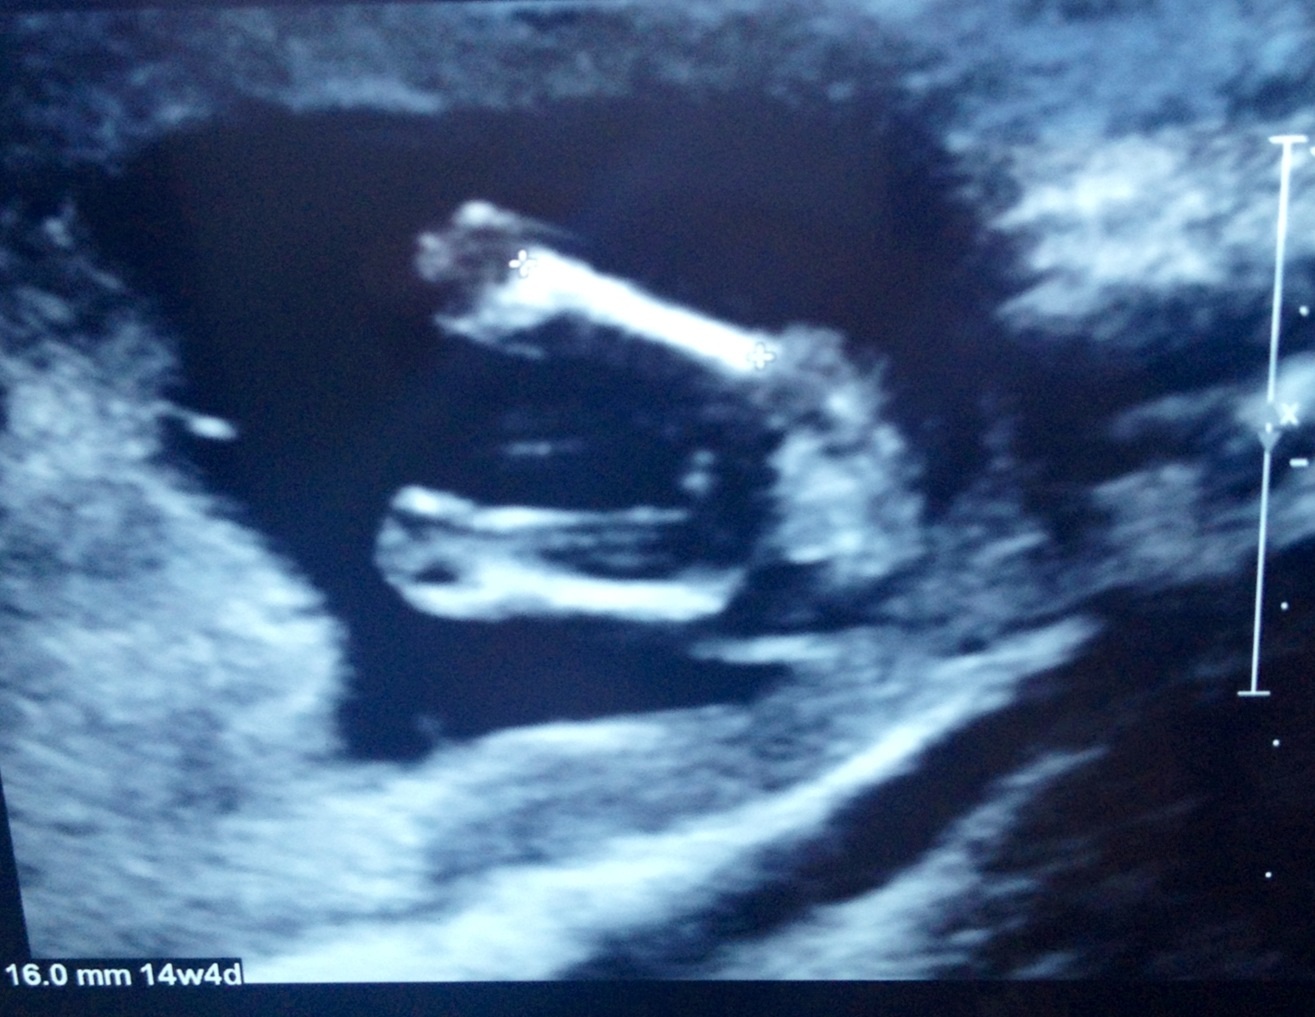

. My uterus was contracting so baby was very squashed!! My scan took over an hour and a half and we still didn't get good pics!! Tech said possibly girl.... Can you make anything out from this pic? This is the best one!! Even skull theory guesses appreciated... I did see the all

Famous white horizontal line while in the scan but no good pics :(Attachment 12534